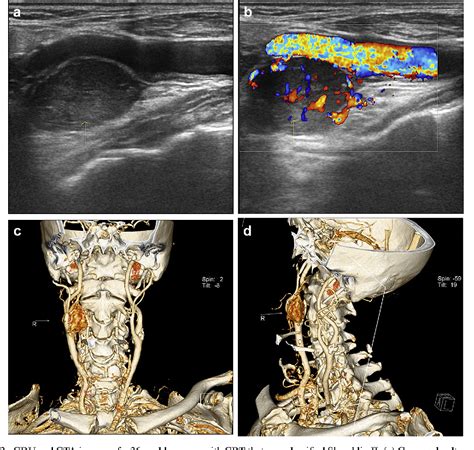

Diagnosing a Carotid Body Tumor requires a combination of physical examination and advanced imaging studies. When a physician suspects such a growth, they typically use specific diagnostic tools to differentiate it from enlarged lymph nodes or other neck masses. The “Lyre sign,” seen on imaging, is a classic finding where the internal and external carotid arteries are splayed apart by the tumor mass.

CT Angiography (CTA) Provides detailed views of the tumor's size and its relationship to major arteries.

Magnetic Resonance Imaging (MRI) Offers excellent soft-tissue contrast to identify involvement of nerves.